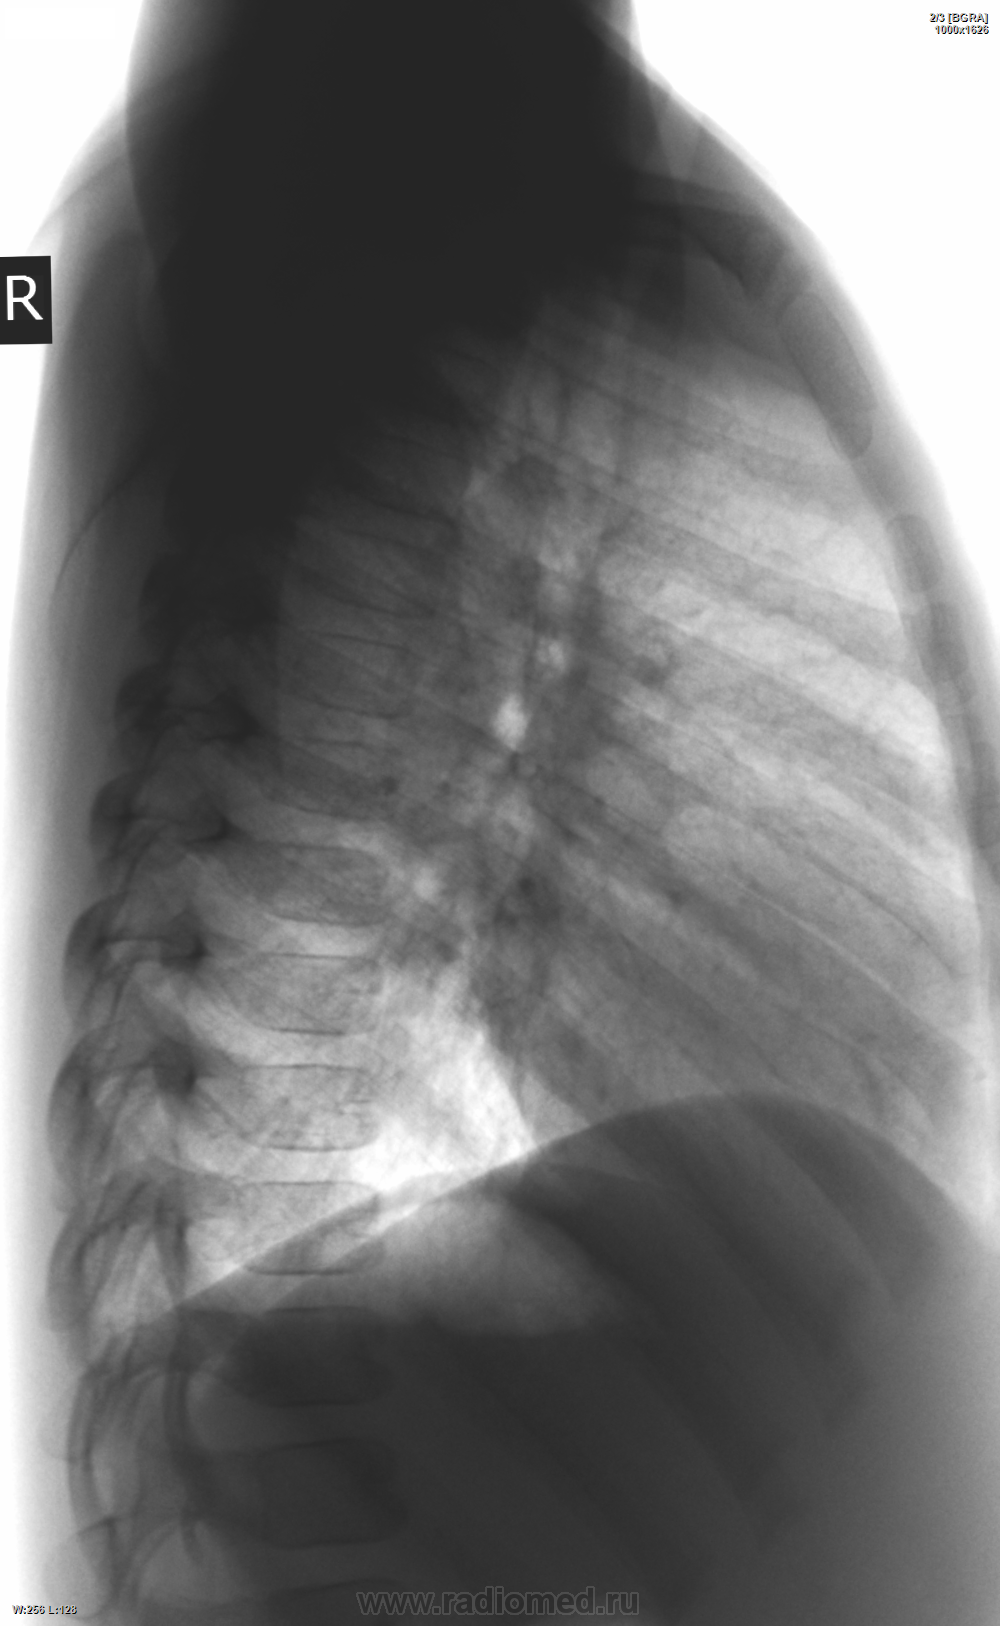

Девочка 1г7м. Кашляет со слов родителей ровно месяц. Выслушаю версии коллег - что это бронхит, ОРВИ, лимфоаденопатия или нормально почти...

Томографировать пока что нет возможности. Но тоже придрался - в правом корне что-то слегка выбухает слабой интенсивности над восходящей аортой. Пока написал ОРВИ, назначил по выздоровлении с архивом контроль...

Ребенка надо обследовать на тбс. Это не так уж сложно, но исключить надо.

Если нет возможности выполнить тмг сейчас ,то можно же направить ребенка в туб диспансер,где выполнят все необходимое.Спокойно можно заподозрить увеличение трахео-бронхиальных л/у справа +кашель в теч.1месяца,возможно,и с-мы интоксикации есть.Напрявляйте.Чего ждать?